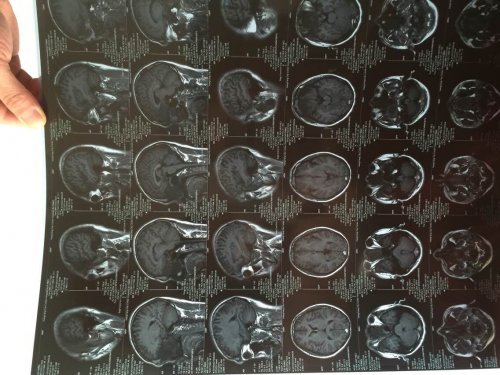

昨日(2015—04—15)MR影像报告:

03—27 影像图:

04—15 影像图

03—27 影像图:

04—15 影像图